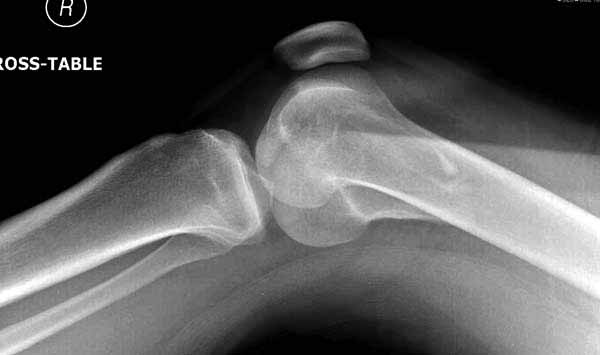

Ответ на эту часть Вашего поста – вложенный файл. Больная оперирована неделю назад по поводу открытого перелома дистального эпиметафиза бедренной кости. После операции она идёт в рентгенкабинет для выполнения послеоперационной контрольной рентгенографии, представленной на слайдах 10 и 11. Узнав, почему её фотографируют, просила передать Вам, Антон, привет.

наружный мыщелок не дорепонироавн - это приводит к вальгусной деформации оси коленного сустава, очень критично для последующей функции.